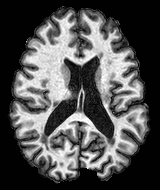

We observed that memberships predicted with an FC layer result in more false positives compared to a fully convolutional network. An example is shown in Fig. 2, where lesion memberships are generated from MPRAGE and FLAIR using the proposed model of convolutional pathways and a comparable model where the last convolutional pathway after concatenation (see Fig. 1) is replaced with a FC layer predicting voxel-wise memberships. The membership image generated with an FC layer, although being close to inside the lesions, has high values () in the left and right frontal cortex where the FLAIR image shows some artifacts. However, the membership obtained with the proposed method shows relatively low values near the frontal cortex.

With FC layer, voxel-wise predictions are performed for each voxel on a new image. Therefore the prediction time for the whole image comprising millions of voxels can take some time even on a GPU, as mentioned in Wachinger et al. (2017). In contrast, with fully convolutional prediction, lesion membership estimation of a mm3 MR volume of size takes only a couple of seconds. Note that although patches are used for training, the final trained model contains only convolution filters and does not depend in any way on the input patch size. Therefore during testing, the lesion membership of a whole 2D slice, irrespective of the slice size, is predicted at a time by applying convolutions on the whole slice. Without an FC layer, the images need not be decomposed into sub-regions, e.g., Kamnitsas et al. (2017). Consequently, there is no need to employ membership smoothing between sub-regions. In addition, since the training memberships, generated by Gaussian blurring of hard segmentations, are smooth, the resultant predicted memberships are also smooth (Fig. 2 last column).